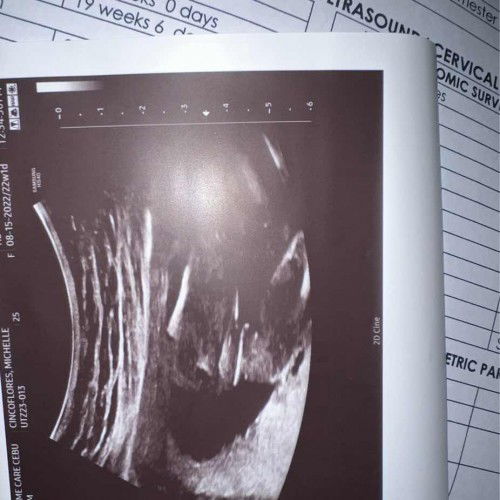

malinaw na Girl po😊yung sakin mamsh boy at hindi ganyan ang itsura. nagsesearch din po ako ng boy ultrasound at tumpak sa CAS ko nung nakaraan na boy yung saken😊 congrats mamsh🥳

di ba nasabi ng OB mo sayo or Sono? sana tinanong mo na. looks like a girl. but not sure.

girl po. malinaw na malinaw